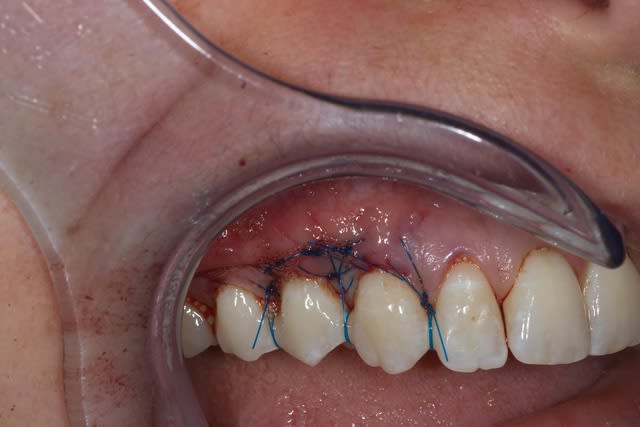

Comme on voit pas bcp de muco sur eugenol

P'tite 23 qui montrait trop de racine

Les 2 dernières photos sont à la dépose des fils (14 jours)

Il y a une "sling suture" pour la traction, le point collé au compo, est en plus, pour tester ;-)

Voici un cas similaire, encore une 23, perte de tissu plus grande, pas de point suspendu avec compo, seulement 2 "sling-suture".

Greffon tracté sous lambeau en mésial et distal comme le cas précédent avec sutures.

Pas d'incision vertical en mésial, surtout que la 22 est un implant, placé trop apical, donc risque de perdre papille distal de 22 +++. Petite incision vertical en distal de 23, pour tracter le lambeau.